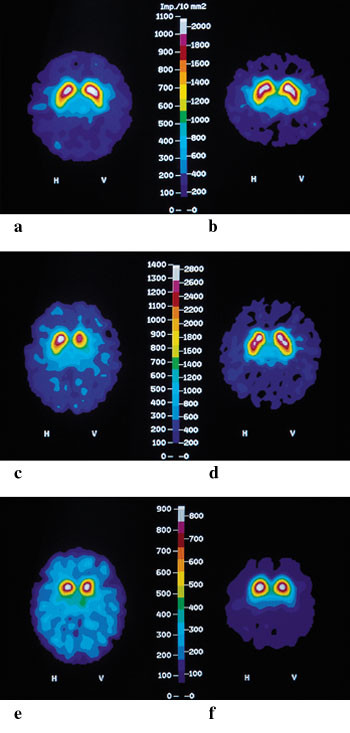

MR cerebrum viste lavsignalforandringer i putamen bilateralt med en hyperintens kant lateralt mot capsula externa og lett generell atrofi kortikalt og sentralt (fig 1a), mens cerebellum var normal (fig 1b). SPECT-undersøkelse med β -CIT viste nedsatt dopaminerg aktivitet i striatum bilateralt, mest uttalt i putamen og relativt symmetrisk (fig 2e). SPECT-undersøkelse med epideprid viste nedsatt D₂-reseptortetthet i putamen og nucleus caudatus bilateralt (fig 2f).

MR cerebrum viste høysignal lateralt og oppad i begge putamen (fig 1c) og markert (og økende) atrofi av cerebellare foliae, vermis cerebelli og av pons (fig 1d). I tillegg var det høysignalforandringer periventrikulært nær sideventriklenes bakhorn. SPECT-undersøkelse med β -CIT viste bilateral betydelig reduksjon av dopaminerg aktivitet, like mye i putamen og nucleus caudatus og mest på venstre side. SPECT-undersøkelse med epideprid var normal.

MR cerebrum viste små, spredte, uspesifikke høysignalområder, ellers ingen sikre patologiske funn. SPECT-undersøkelse med β -CIT viste uttalt reduksjon av dopaminerg aktivitet i striatum bilateralt, mest på høyre side. SPECT-undersøkelse med epideprid viste lett nedsatt D₂-reseptortetthet i nucleus caudatus, men normal i putamen.

Selv om sensitiviteten for påvisning av Parkinsons sykdom ved SPECT-undersøkelse med β -CIT er meget høy, er spesifisiteten lav når man bare vurderer grad av redusert dopaminopptak i striatum. Det viser seg imidlertid at mens dopaminopptaket hos pasienter med Parkinsons sykdom særlig er redusert i putamen og oftest asymmetrisk på de to sider, er det hos pasienter med Parkinson-pluss-syndrom og særlig ved progressiv supranukleær parese en mer symmetrisk reduksjon i hele striatum, inkludert nucleus caudatus (9, 16). Alle våre tre pasienter hadde patologiske funn ved SPECT-undersøkelse med β -CIT med tendens til mer proposjonal affeksjon i caudatus og putamen enn man ser hos pasienter med Parkinsons sykdom (fig 2c, 2e). Hos pasient 3 var affeksjonen mer uttalt enn man ser ved Parkinsons sykdom av like lang varighet.

For å bedre spesifisiteten har man også undersøkt den postsynaptiske siden av dopaminerg transmisjon i striatum; D₁- og D₂-reseptorene. Det er redusert stimulering av D₂-reseptorer som antas å være av størst betydning for opptreden av motoriske parkinsonistiske symptomer, og det er derfor disse man særlig har undersøkt med PET og SPECT-undersøkelse.123I-epideprid er en av ligandene som binder seg til D₂-reseptorene, og som benyttes ved SPECT-undersøkelse av disse (17). Undersøkelser av pasienter med Parkinson-pluss-syndrom har vist redusert D₂-reseptortetthet i gjennomsnitt for hele gruppen av pasienter, men noen av dem ligger innenfor det normale referanseområdet (17 – 19). Påvisning av signifikant nedsatt D₂-reseptortetthet i striatum, som hos pasient 1 (fig 2f), gir derfor støtte til diagnosen Parkinson-pluss-syndrom og taler imot diagnosen Parkinsons sykdom. Normal eller forhøyet D₂-reseptortetthet i striatum ved SPECT-undersøkelse, som man ser ved Parkinsons sykdom og som vi fant hos pasient 2, utelukker likevel ikke at det foreligger et Parkinson-pluss-syndrom. Hos pasient 2 er det særlig klinisk utforming og MR-funn som taler for olivopontocerebellar atrofi, mens man hos pasient 3 må støtte seg først og fremst til kliniske tegn samt de uttalte forandringene ved SPECT-undersøkelse med β -CIT.